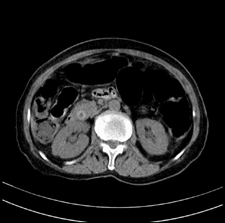

患者,女,75岁。腹痛,体黄5日,膝胸位时腹痛缓解。肝功能明日出来。彩超提示胆总管占位,未见血流信号。心电图提示s-t段改变。患者体质较弱,未能增强。

胆总管结石

胆总管多发结石

胆总管多发结石伴肝内外胆管轻度扩张。

胆总管上段,腔内有软组织密度影 ,ct值36-44hu。大家看有没有胆管癌的可能。

典型胆总管多发结石;增强扫描前后ct值是否发生改变是鉴别结石与占位的依据。